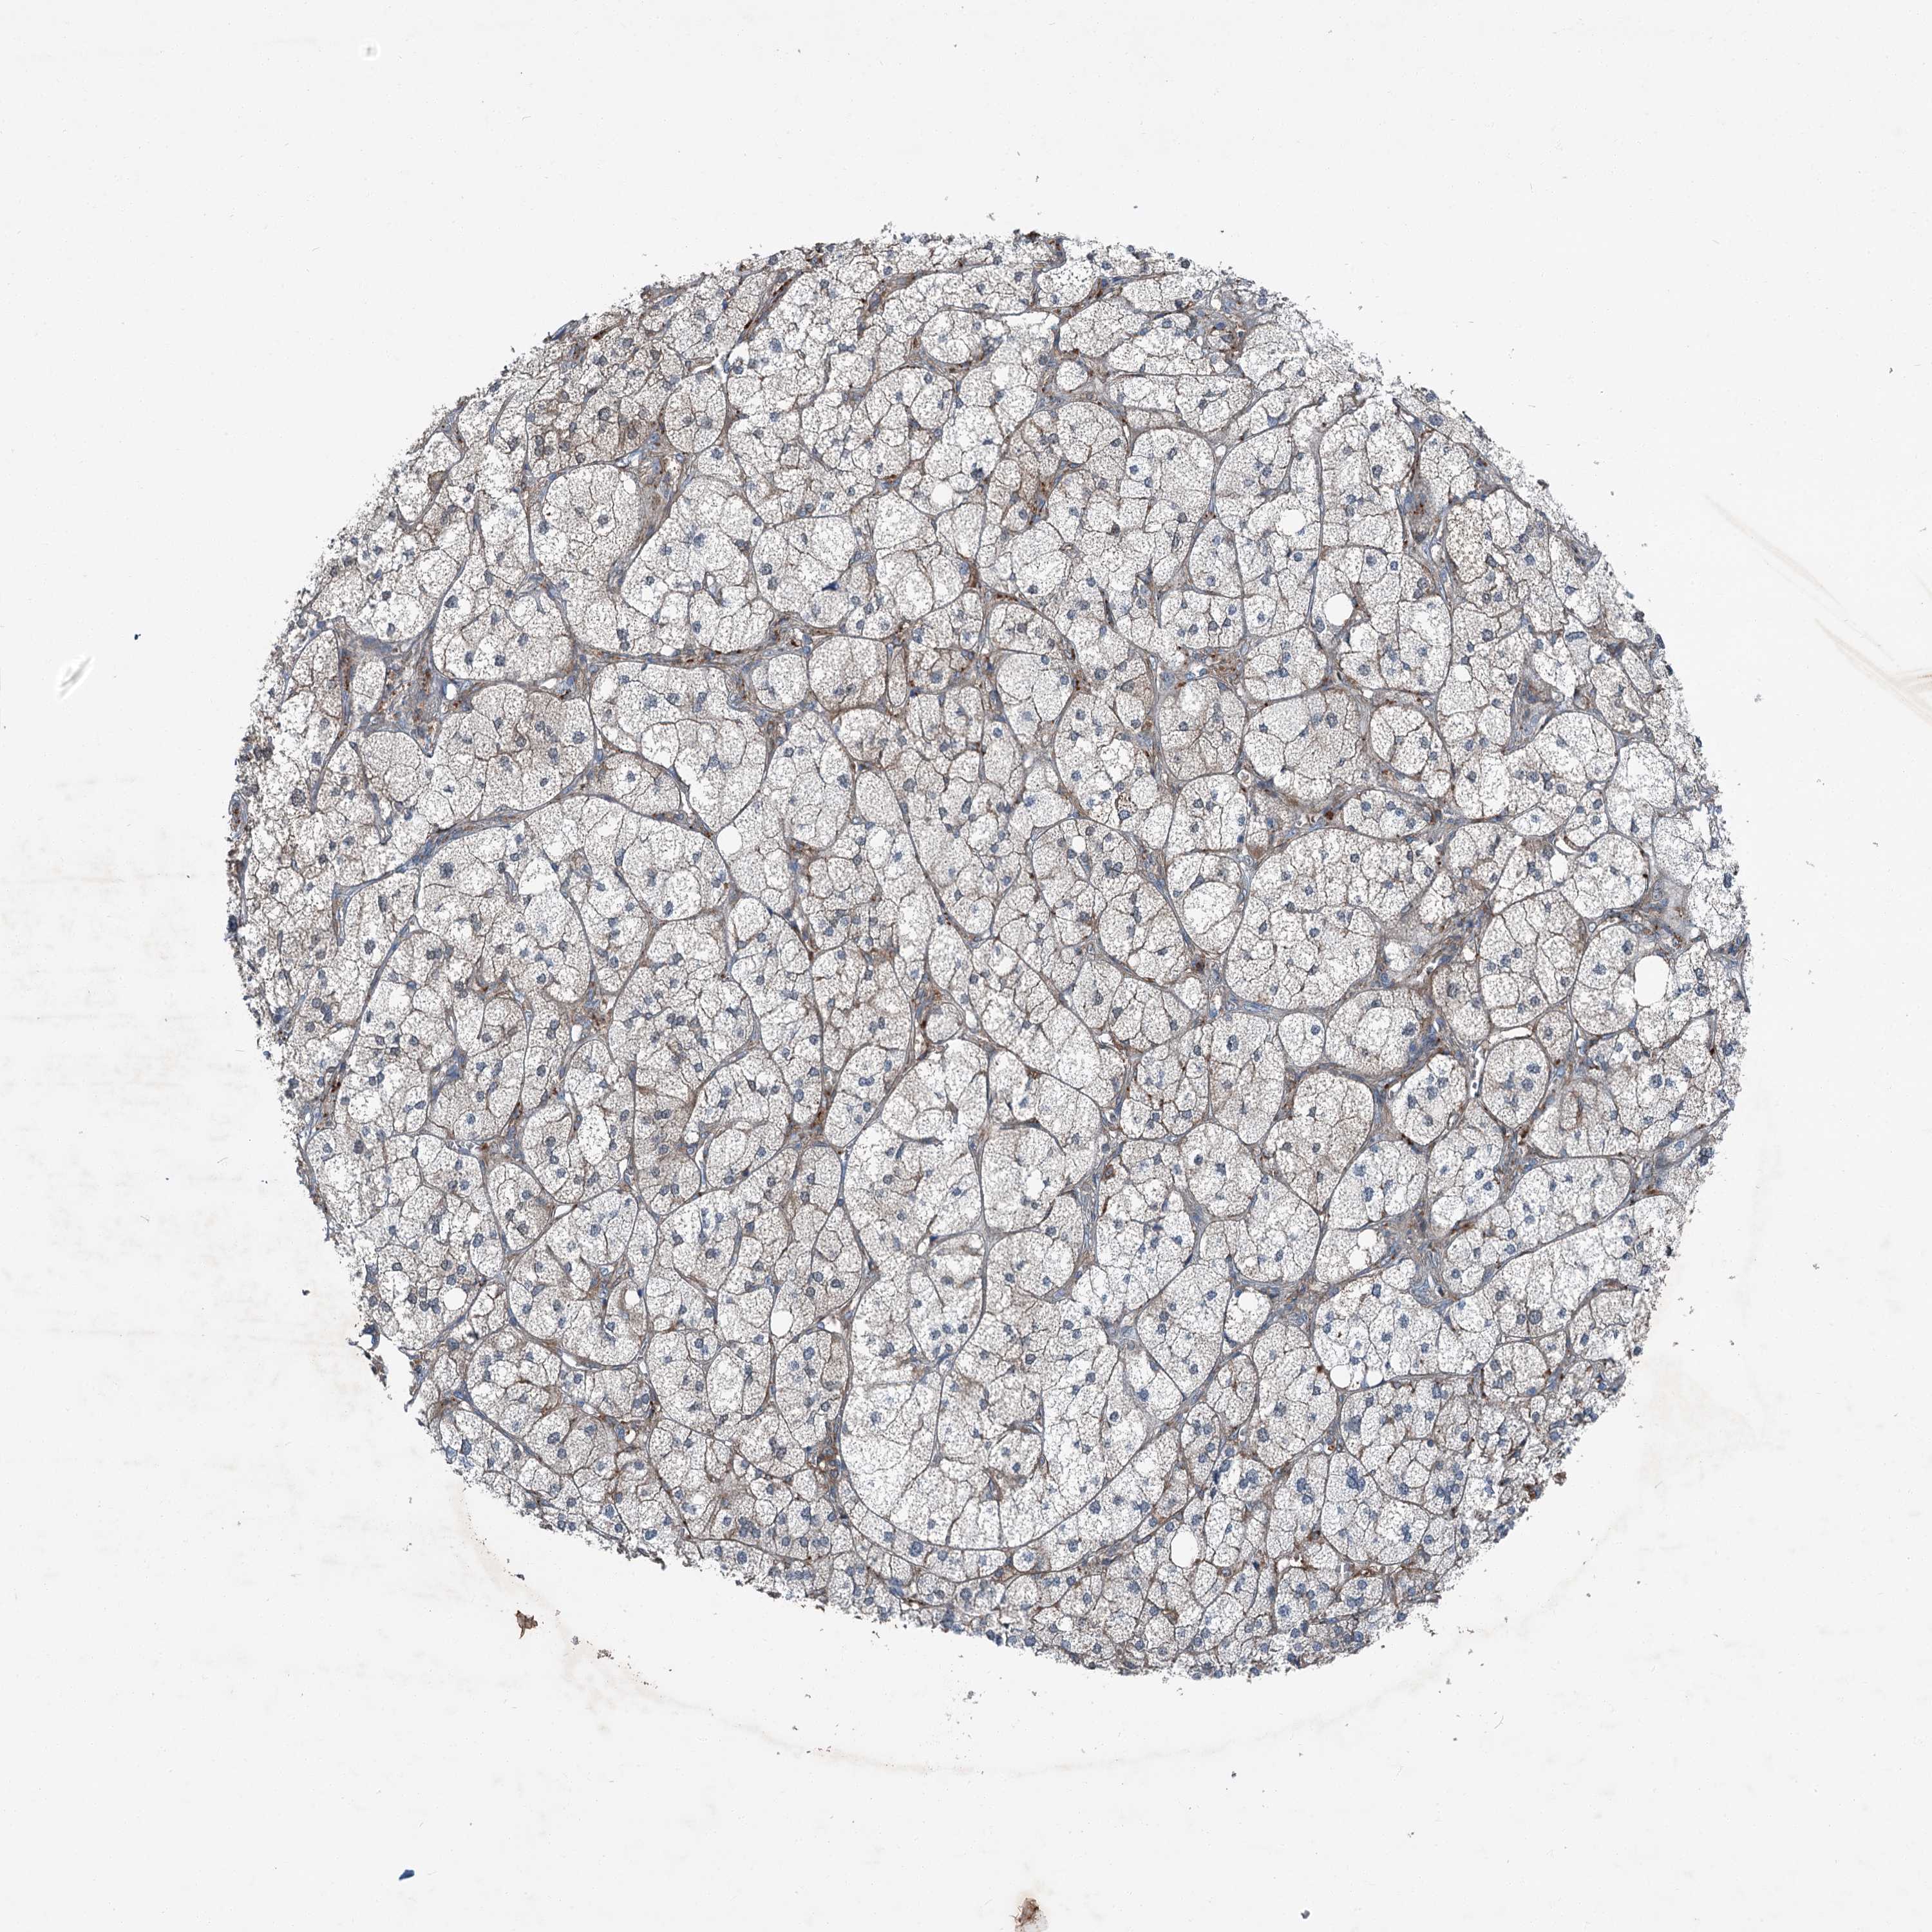

ADRENAL GLAND - Antibody stainingi

Antibody staining in the annotated cell types in the current human tissue is reported as not detected, low, medium, or high, based on conventional immunohistochemistry profiling in selected tissues. This score is based on the combination of the staining intensity and fraction of stained cells.

Each image is clickable and will lead to virtual microscopy that enables deeper exploration of all samples and also displays staining intensity scores, fraction scores and subcellular localization as well as patient and tissue information for each sample.

Antibody HPA037422Antibody HPA037423Antibody CAB032501

Glandular cells Not detectedNot detectedMedium